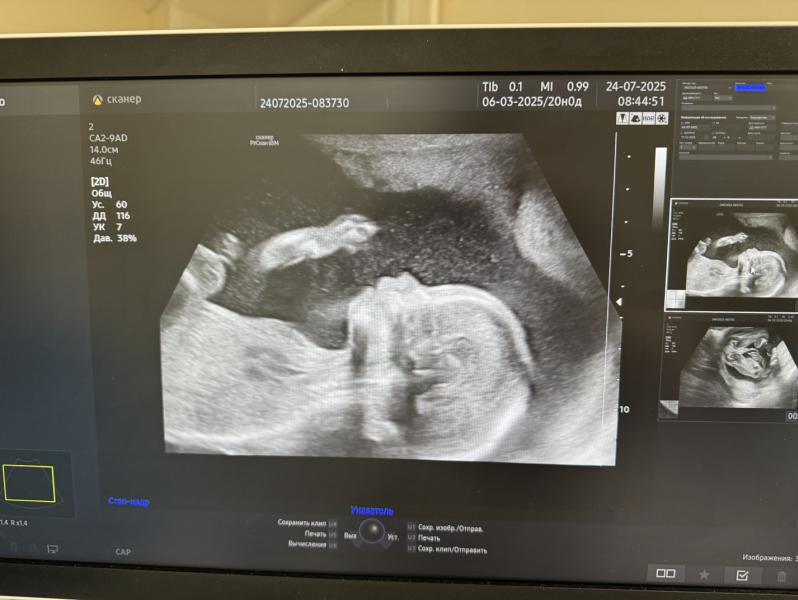

Сегодня прошли второй скрининг😍

В 17 недель была небольшая отслойка плаценты, сейчас уже все хорошо, на узи сказали, что вообще не заметно, что она была😄

Очень уж я ждала девочку🥹до такой степени, что у меня снова будет мальчик😄🥳но ни капли грусти, будут у меня два пацана, два моих защитника😎